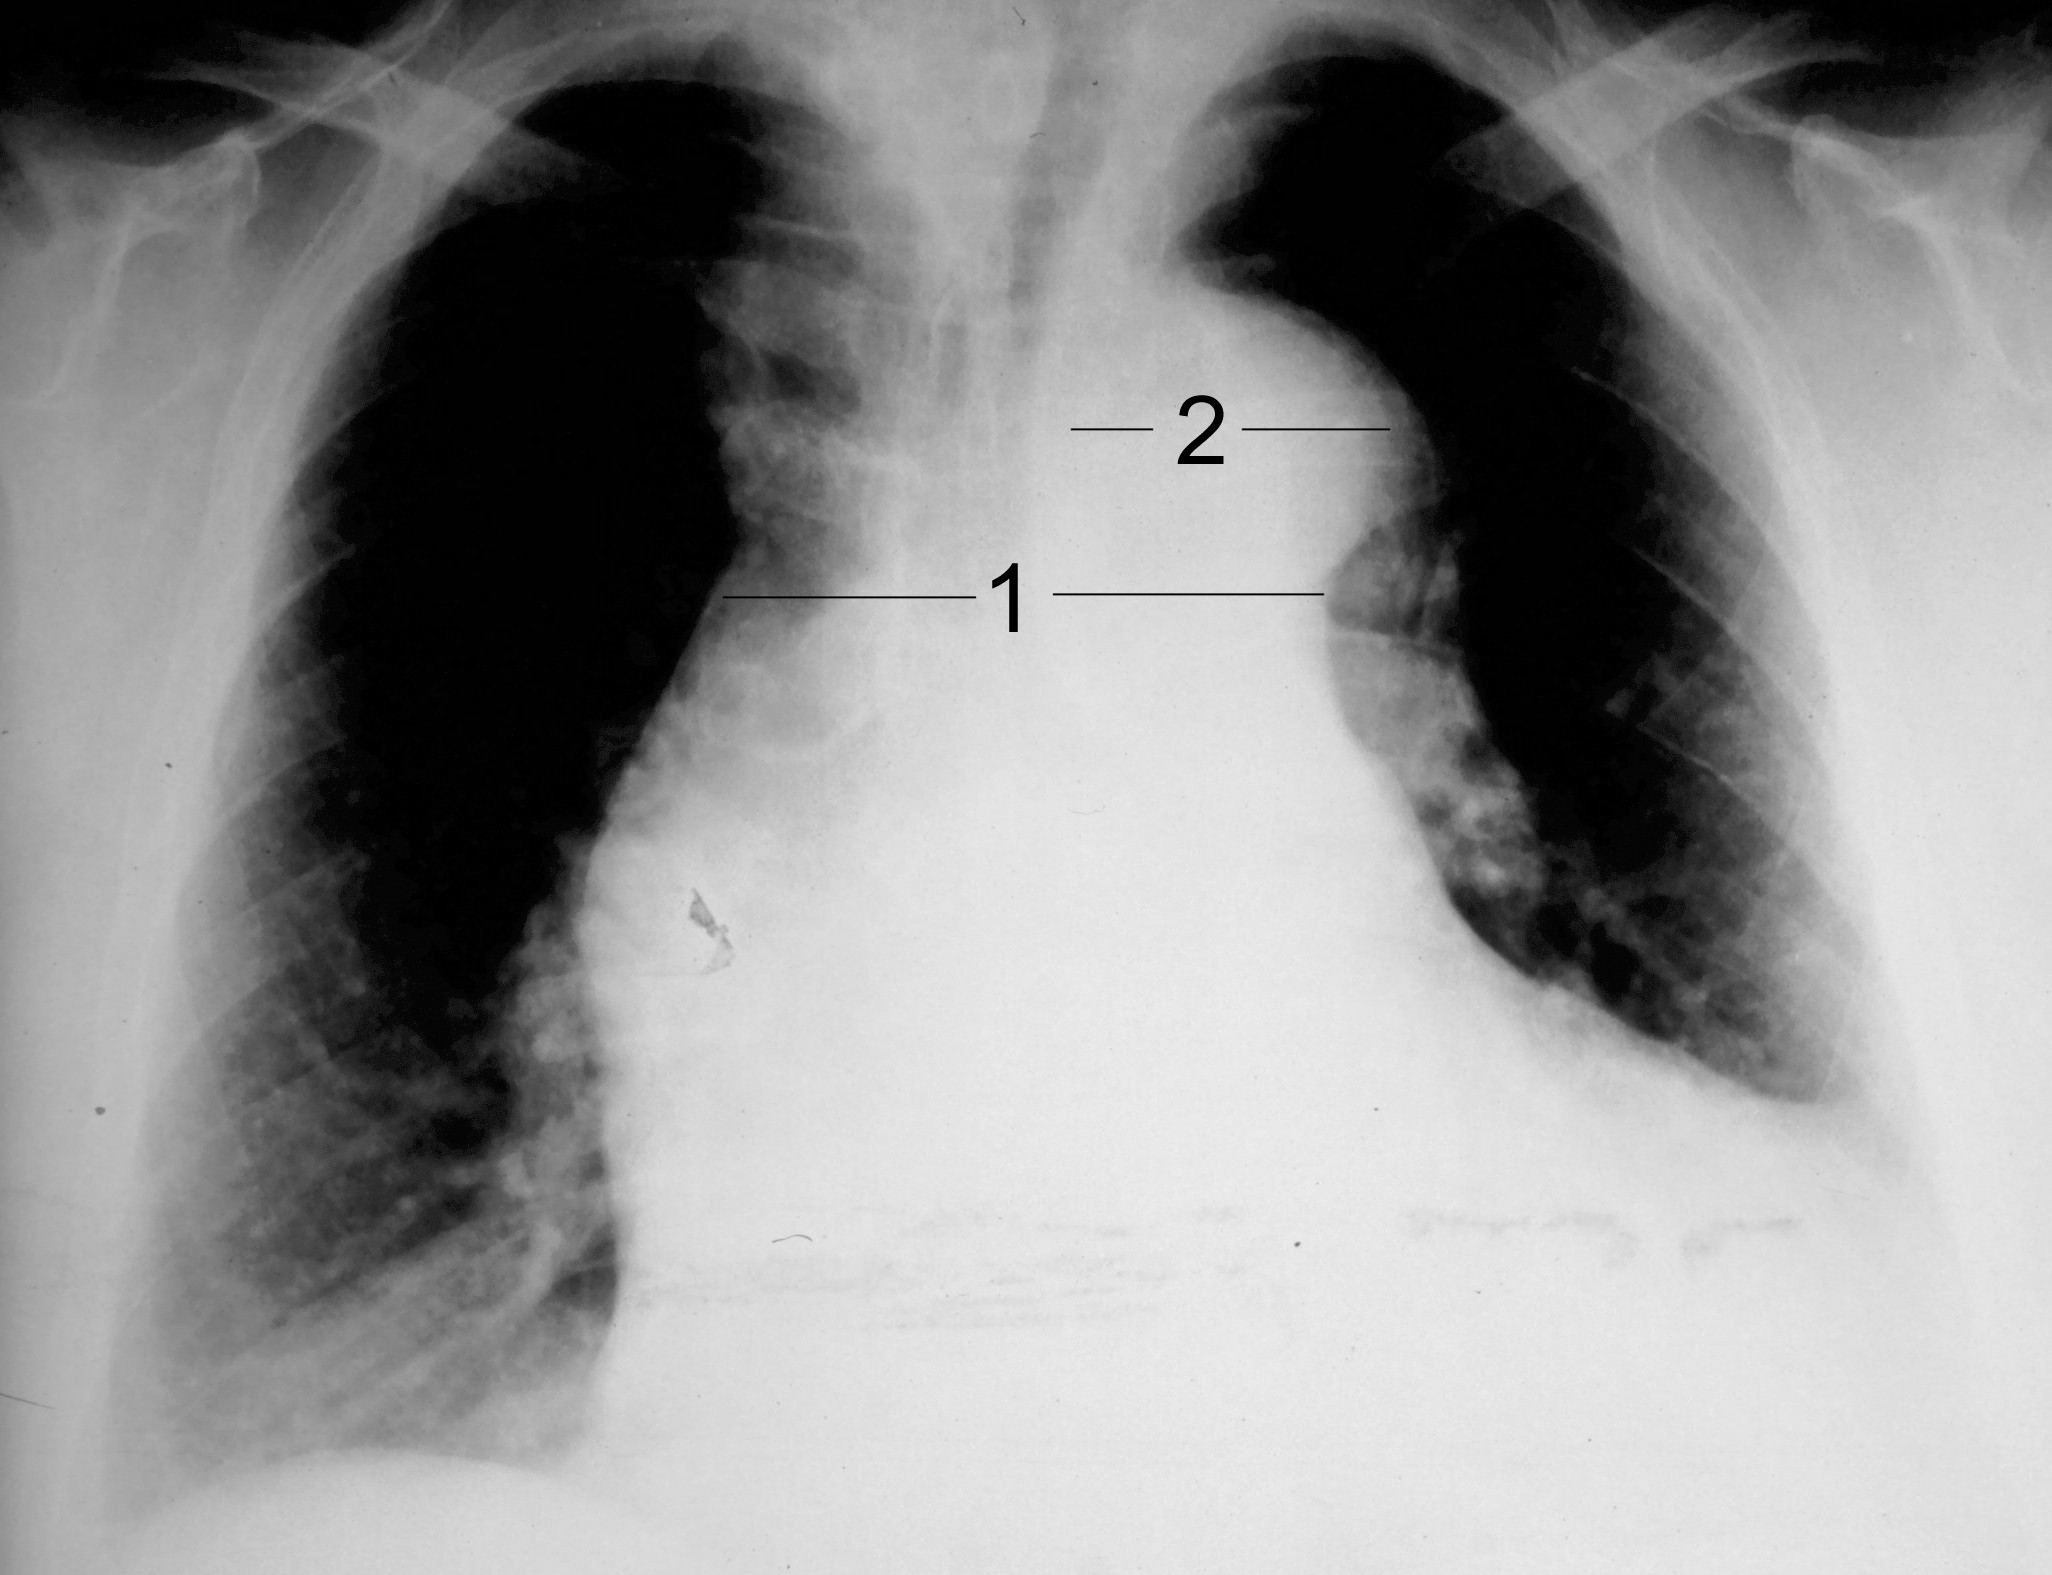

흉막 삼출액(폐와 흉벽 또는 횡격막 사이의 공간에 체액이 고인 상태)은 대동맥의 일시적인 파열로 인한 혈액이나 대동맥 주변의 염증 반응으로 인한 체액으로 인해 발생할 수 있다. 대동맥 박리로 인해 흉막 삼출액이 발생할 경우, 오른쪽 흉강보다는 왼쪽 흉강에서 더 흔하게 나타난다.[19]

흉부 방사선 촬영은 대동맥 박리에서 나타날 수 있는 흉부 대동맥의 형태 변화를 보여줄 수 있다. 전형적으로, 방사선 사진에서 종격동의 새로운 확장 소견은 상행 대동맥 박리를 감지하는 데 중간 정도의 민감도를 보이지만, 다른 많은 질환이 종격동의 명백한 확장을 유발할 수 있으므로 이 소견은 특이도가 낮다.

다음과 같은 다른 방사선학적 소견들이 관련되어 있다.

- "칼슘 징후"는 내막 석회화가 외부 대동맥 가장자리에서 10mm 이상 분리된 것처럼 보이는 것을 나타낸다.

- 흉수는 하행 대동맥 박리에서 더 흔하게 나타나며, 전형적으로 좌측에 발생한다.

- 기타 소견: 대동맥 융기 소실, 좌측 주 기관지 압박, 기관 주위 선 소실, 기관 편위.

중요한 것은, 대동맥 박리의 약 12~20%는 흉부 방사선 사진으로 감지할 수 없다는 것이다. 따라서 "정상" 흉부 방사선 사진은 대동맥 박리를 배제하지 못한다. 임상적 의심이 높은 경우, 보다 민감한 영상 검사(컴퓨터 단층 촬영 혈관 조영술, 자기 공명 혈관 조영술, 또는 경식도 심장 초음파)가 필요할 수 있다.